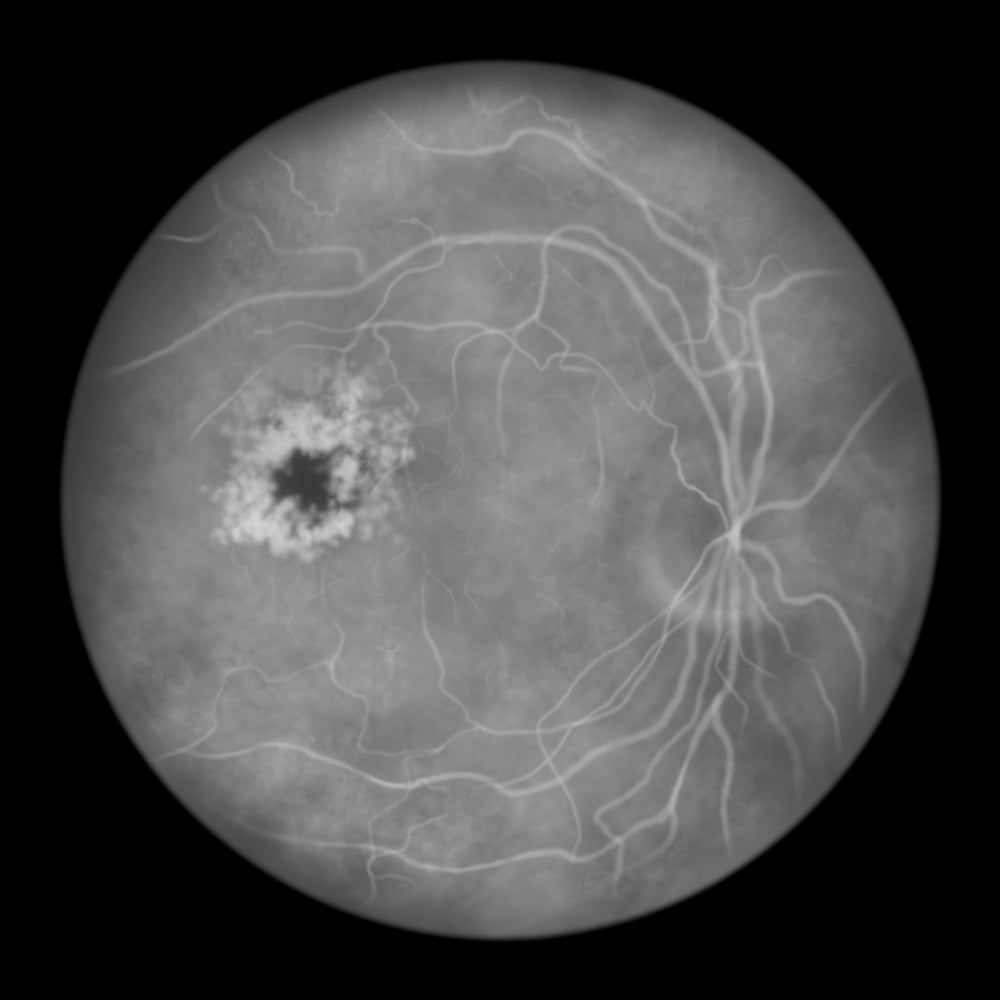

Fluorescein Angiography

- Fluorescein angiography to assess retinal blood flow and detect leaking or blocked vessels